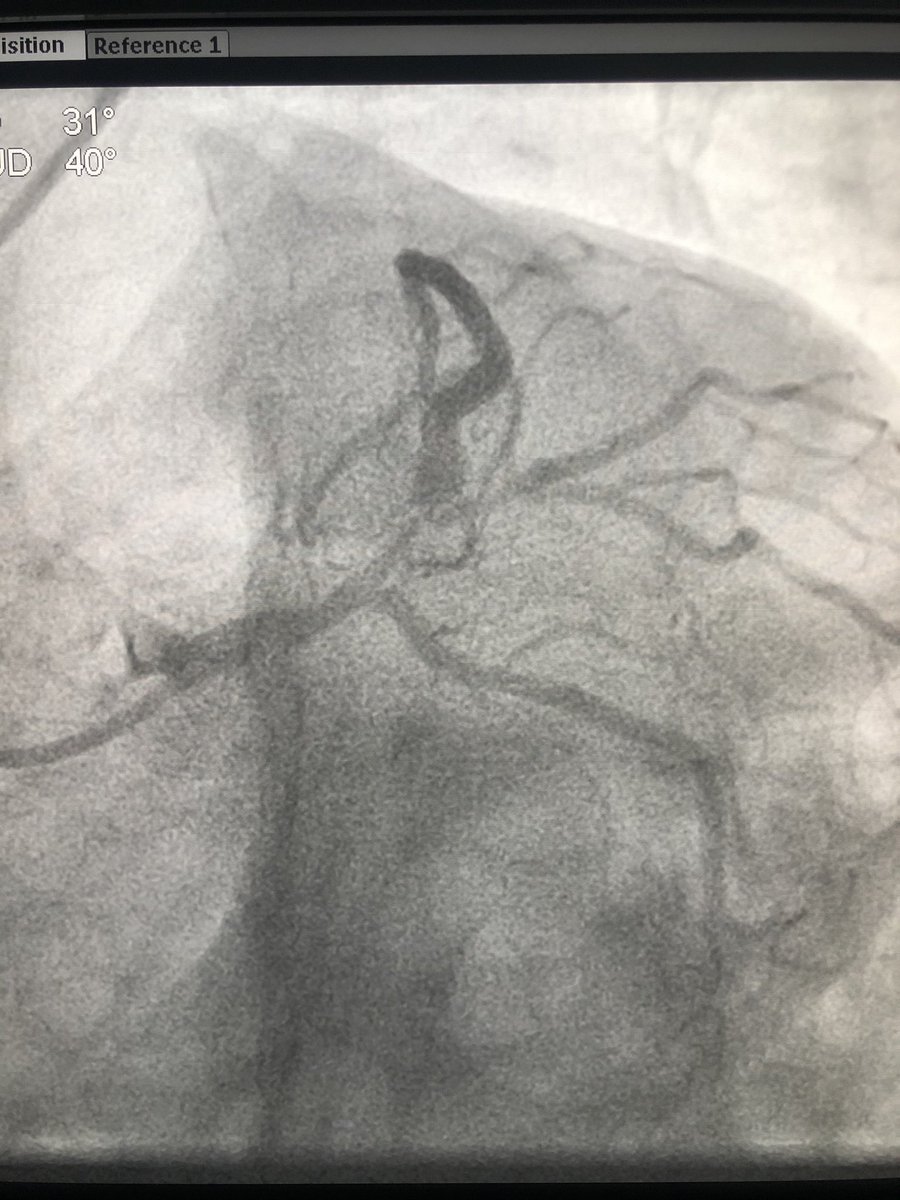

Advised a coronary angiography. He got admitted the next day and angio showed critical left main disease and triple vessel disease. #leftmainCAD